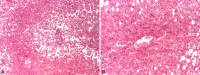

Worldwide, nonalcoholic fatty liver disease (NAFLD) has emerged as the leading cause of chronic liver disease in children and adolescents, but also as a real public health issue. Over the last decades, the increase in the rates of obesity and overweight in children has led to the increase in the worldwide prevalence of pediatric NAFLD. Detection of a hyperechoic appearance of the liver at ultrasounds or elevated levels of transaminases, identified during a routine control in children, suggests NAFLD. The disorder can be diagnosed with either non-invasive strategies or through liver biopsy, which further allows the identification of specific histological aspects, distinct from those found in adults. Since NAFLD is a clinically heterogeneous disease, there is an imperative need to identify noninvasive biomarkers and screening techniques for early diagnosis in children, in order to prevent metabolic and cardiovascular complications later in adulthood. This review emphasizes the main diagnosis tools in pediatric NAFLD, a systemic disorder with multifactorial pathogenesis and varying clinical manifestations.